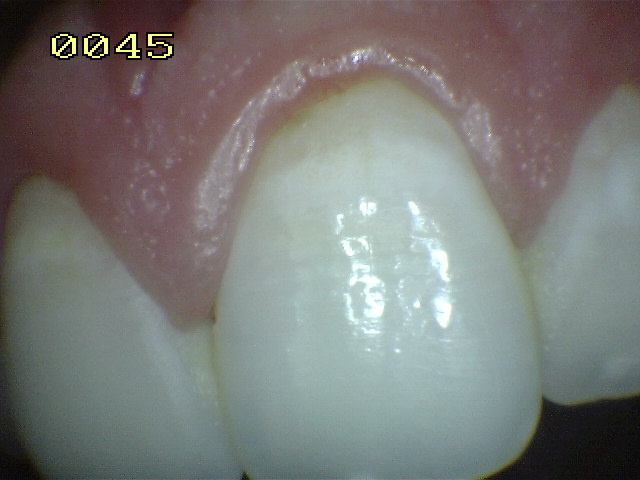

Encía Normal |

Encía levemente inflamada con un

componente fibroso. Observe el borde gingival con aspecto

liso, turgente y brillante de color rojo |